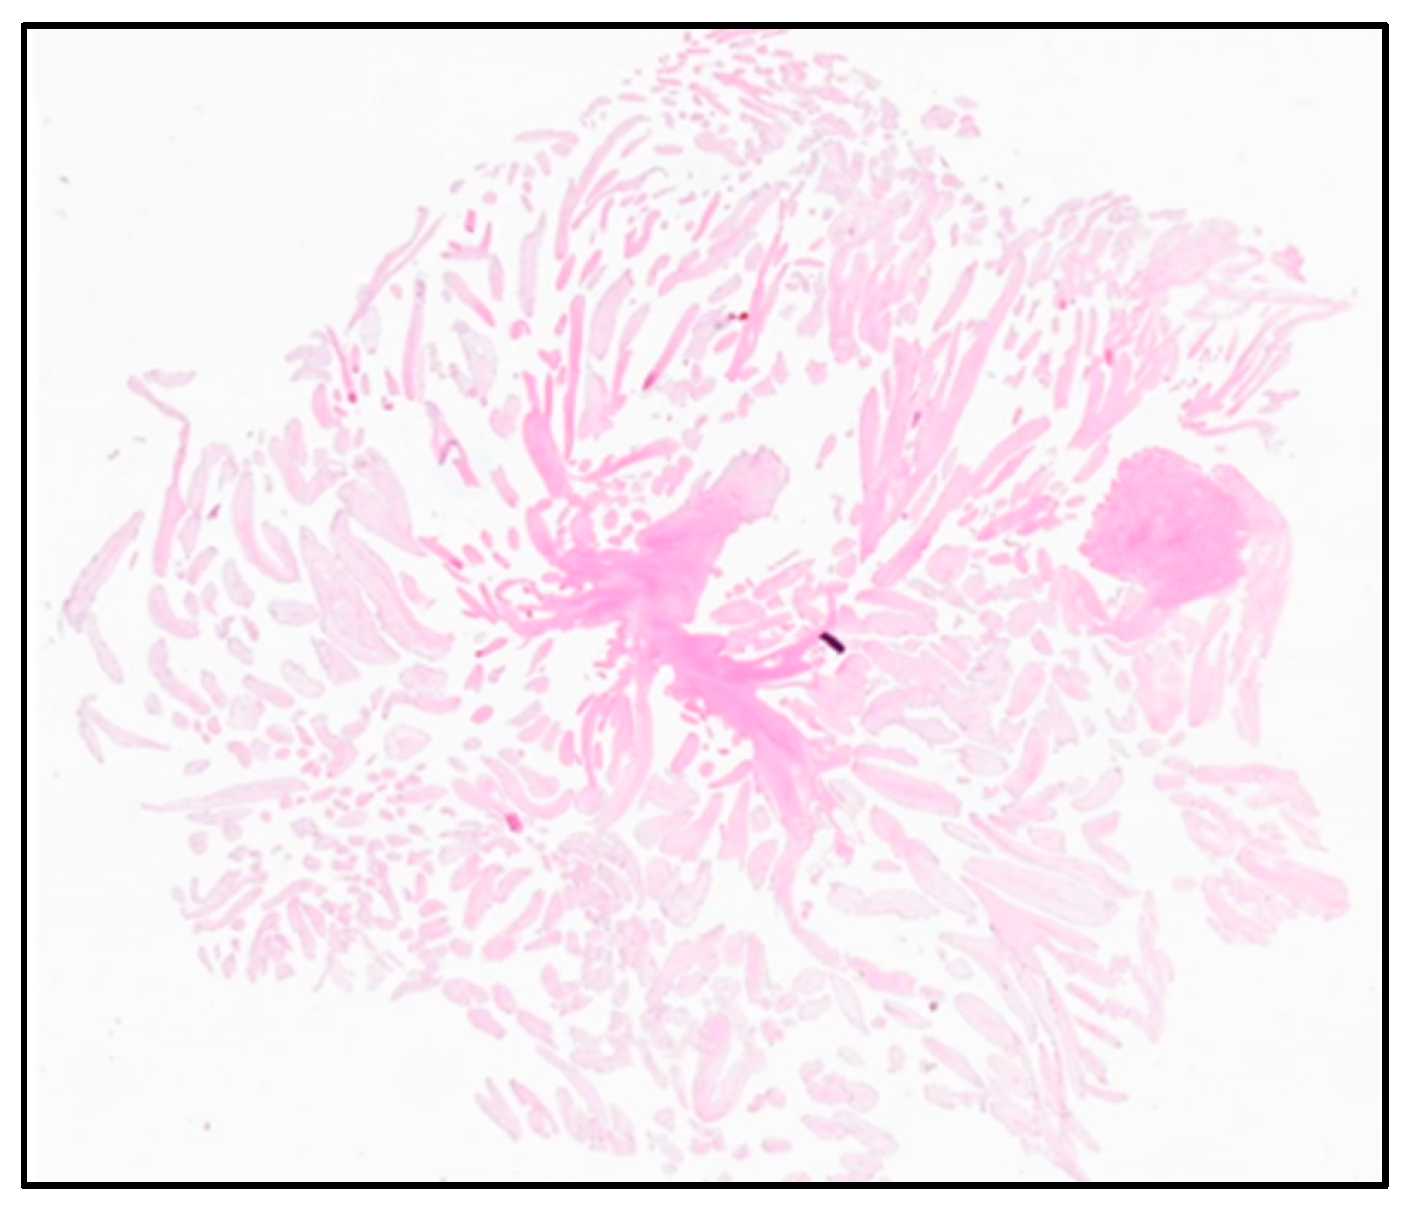

2.3. Outcomes